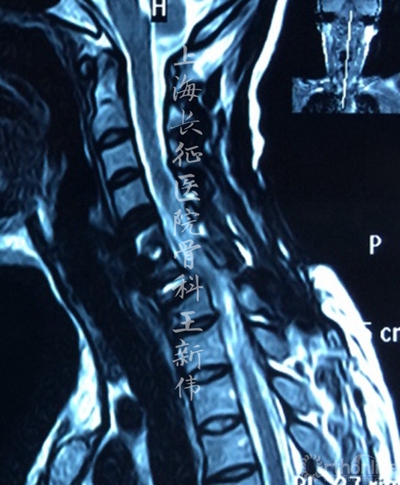

颈椎MRI平扫:

第二次术前颈椎MRI平扫,可见C6/7存在成角畸形,脊髓受压